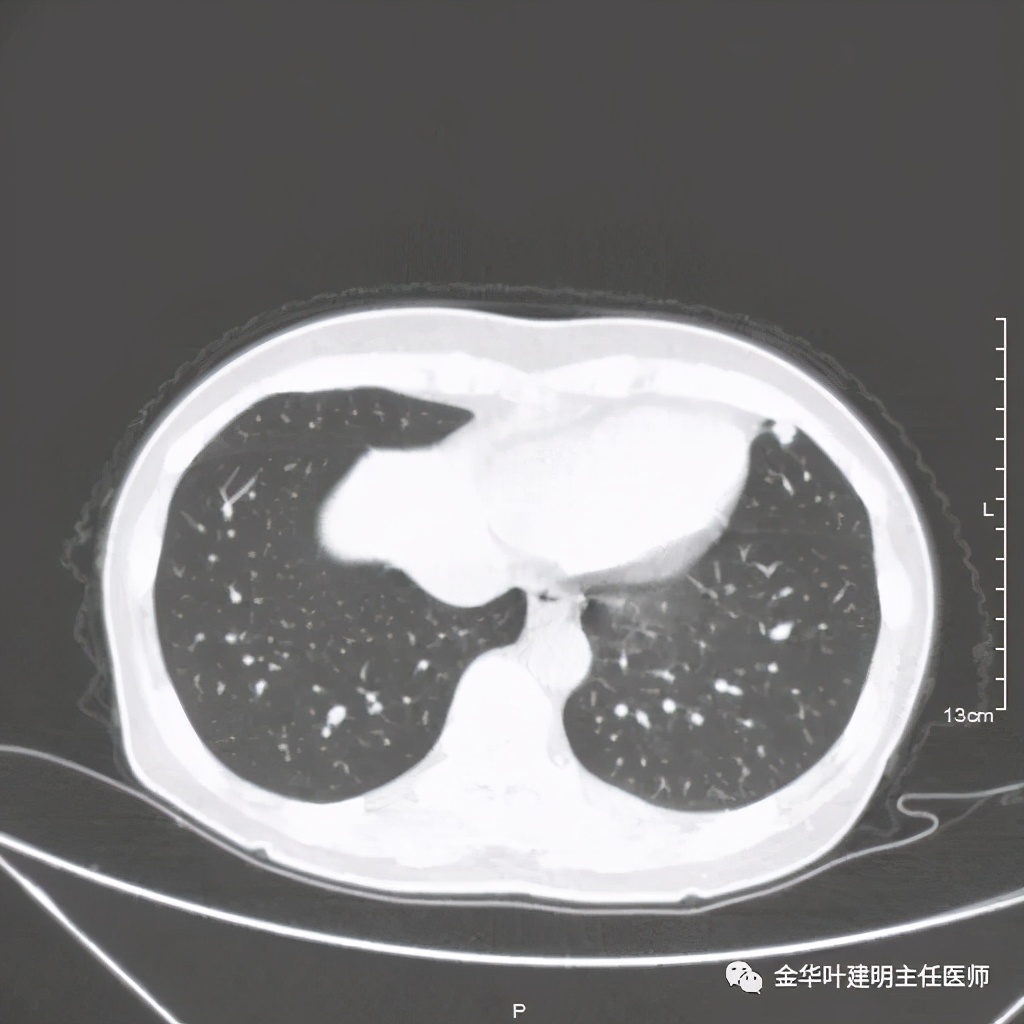

六、神经内分泌癌(此例为不典型类癌,小细胞癌以后再总结):

影像特征:不典型类癌一般圆形生长,实性,边缘比较光滑,但硬度不够。侵蚀力也不够。就像这例,我们发现其与肺动脉接触的地方,居然无法推压血管,反而肿瘤被血管占据了其生长的位置,在支气管内,肿瘤也是对支气管壁没有造成明显的破坏。也就是说 圆形边清较软、侵蚀力弱的实性结节 要考虑类癌的可能性。